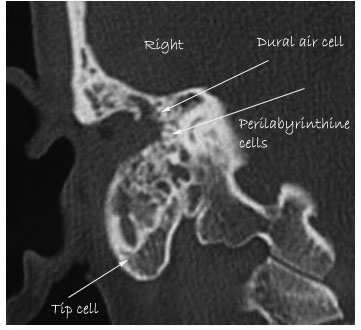

HRCT image of temporal bone showing pneumatization

3. Perilabyrinthine: Supralabyrinthine and infralabyrinthine

This tract pneumatizes the labyrinthine area. It divides into supralabyrinthine and infra labyrinthine tracts.